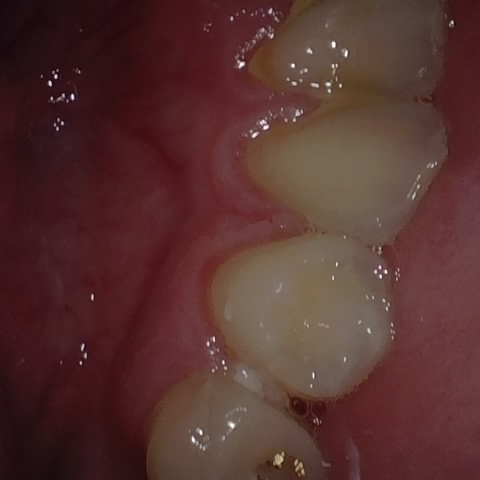

Annotated as "Good"